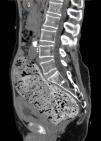

Fecaloma as a cause of acute renal failure